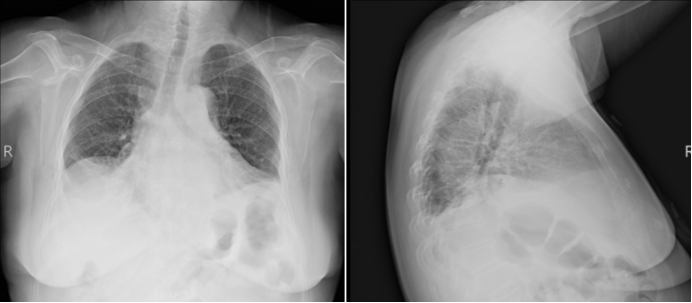

• CT肺动脉造影(CTPA)(图1)①多发肺动脉分支显影浅淡,多考虑肺内实变压迫管腔所致;心影增大;主动脉硬化;②双肺多发斑片状稍高密度影伴部分实变影,双肺下叶为著,考虑炎症可能;③纵隔心影右侧旁斑片状稍高密度影,心包囊肿或肿瘤性病变待排;④肝脏密度减低,考虑脂肪肝;⑤胸椎退行性变。

图片

1  患者CTPA图像(2025-06-10)

注:红框部分,笔者会诊时考虑为膈肌抬高、肺不张。